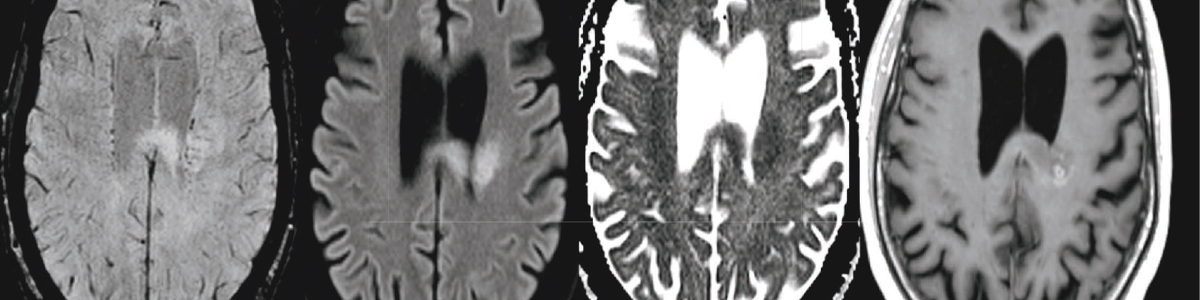

A. ANGIOGRAFI

Angiografi betyder inget annat än avbildning av kärl, och många olika tekniker ryms i detta breda koncept. I neuroradiologiska sammanhang skiljer vi på konventionell angiografi, DT-angiografi och MR-angiografi. Vi behöver även hålla isär venografier från arteriografier, så det i folkmun slarviga ”angio” har massor av tänkbara betydelser och är ett påtagligt

kontextkrävande ord med stor potential för att orsaka missförstånd.

Låt oss börja med konventionell angiografi, där det konventionella står för sättet vi applicerar röntgenstrålning, det vill säga att vi erhåller en tvådimensionell bild eller bildserie av en genomlyst patient. Dessa undersökningar sker efter arteriell kateterisering, oftast av en interventionist. Innan de tomografiska metoderna kom att dominera specialiteten

var angiografier en vanlig arbetsuppgift för en neuroradiolog. Många av oss som på senare tid utbildats inom diagnostisk neuroradiologi har liten eller ingen praktisk erfarenhet av detta. Kontrastmedlen som används är jodbaserade, precis som vid datortomografi. Angiografin kan göras mer selektiv genom att katetern förs till en mer perifer artär inför injektionen. Konventionell angiografi har en mycket hög spatiell upplösning vilket tillåter analys även av mycket små kärl (såsom hypoplastiska kommunikanter), och misstänkta aneurysm kan bedömas med hög säkerhet. Diskreta kaliberväxlingar kan påvisas, exempelvis vid vasospasm och vaskulit.

Tidsförloppet för kontrastmedlets omsättning låter sig fångas i genomlysning eller i en bildserie, från stora artärer till arterioler, kapillärer och över till det venösa systemet. Detta innebär att fistlar och arteriovenösa missbildningar kan identifieras, och dess uppbyggnad med tillförande och avförande kärl kan kartläggas. Digital subtraktionsangiografi (DSA) innebär att en vanlig röntgenbild tas innan kontrastmedlet injiceras, varpå skelettet kan subtraheras från bilden och blodkärlen framhävas. Med modern teknik kan tredimensionella rekonstruktioner erhållas även vid konventionell angiografi.